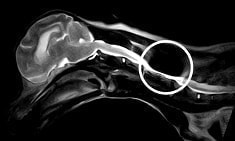

MRI撮影の障害になる可能性

マイクロチップには金属が含まれています。

したがって、磁気で撮影するMRI検査で画像が乱れてしまうことがあります。

しかし、撮影部位がチップ挿入部位から離れていれば問題はありません。

MRI画像

マイクロチップがある部位の画像が歪んでいます